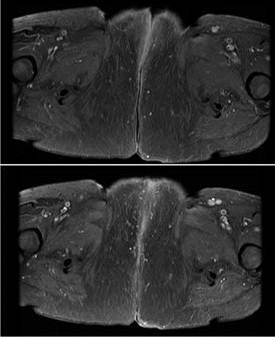

Se ofrece manejo local con radioterapia externa 50 Gy mas braquiterapia endocavitaria total 48 Gy. Presenta recurrencia local a los 7 meses de tratamiento siendo la misma irresecable. (fig 1) por lo que se inicia tratamiento sistémico con carboplatino AUC de 5 y paclitaxel a 175 mg/m2 . Tras 6 ciclos de tratamiento con respuesta parcial y disminución de más del 50% (figura 2B). La RNM con disminución de más del 80% de la lesión vulvar. (Fig. 2). Actualmente se encuentra en vigilancia, con mejoría clínica del dolor y la ulceración.